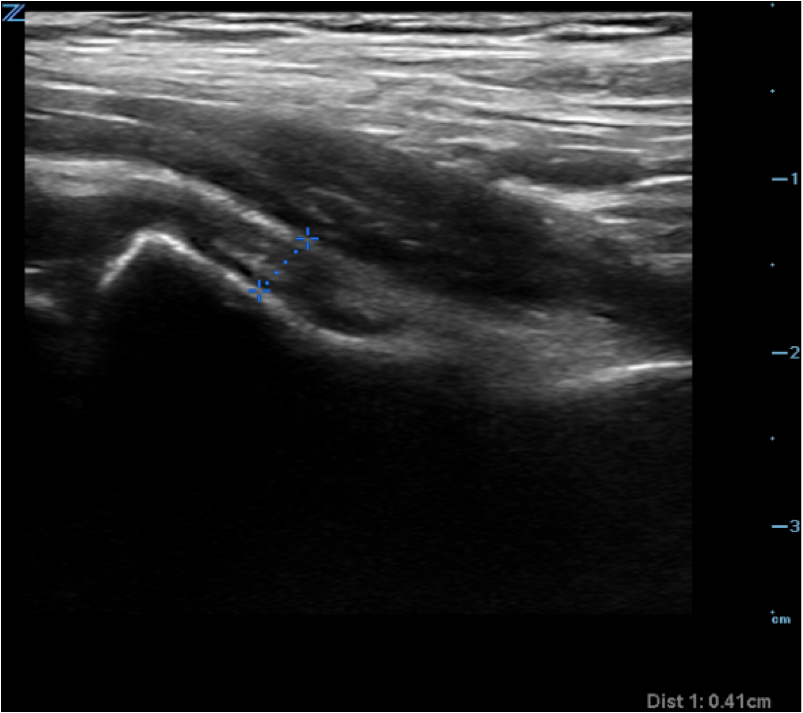

- Figure 3. Measurement of hip joint fluid thickness

- Measure thickness of joint (area from periosteum to outer joint capsule just deep to iliopsoas muscle) at the femoral neck.